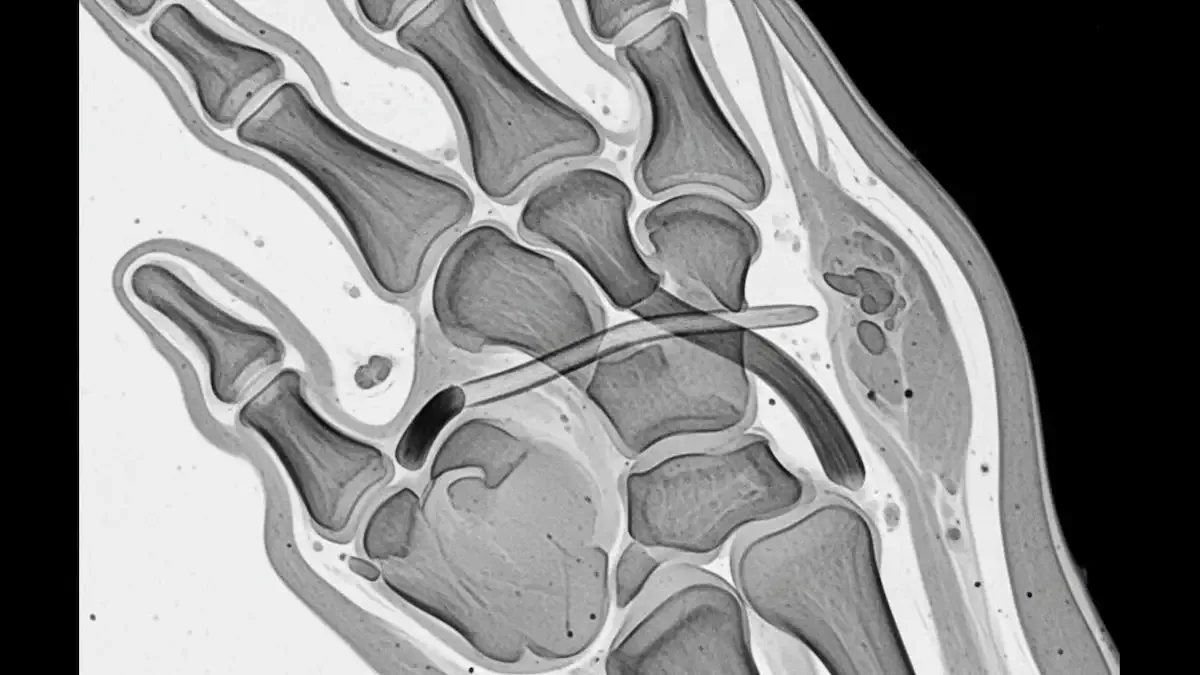

Torção No Dedo Da mão: O Que Fazer E Quando Tratar

A torção no dedo da mão é uma lesão frequente tanto em esportes quanto em situações do dia a dia. Um movimento brusco, uma pancada direta ou a rotação forçada do dedo já são suficientes para comprometer os ligamentos da articulação. Mesmo quando o...